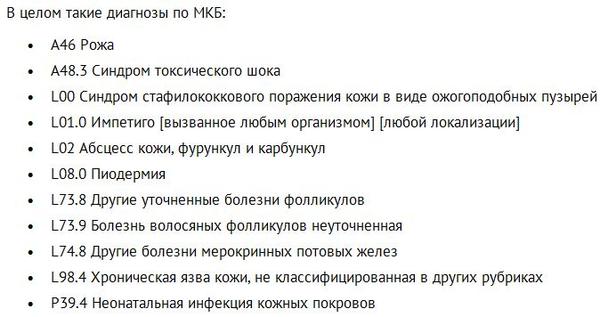

Код мкб 10 атерома головы

Код мкб 10 атерома головы 109 фото